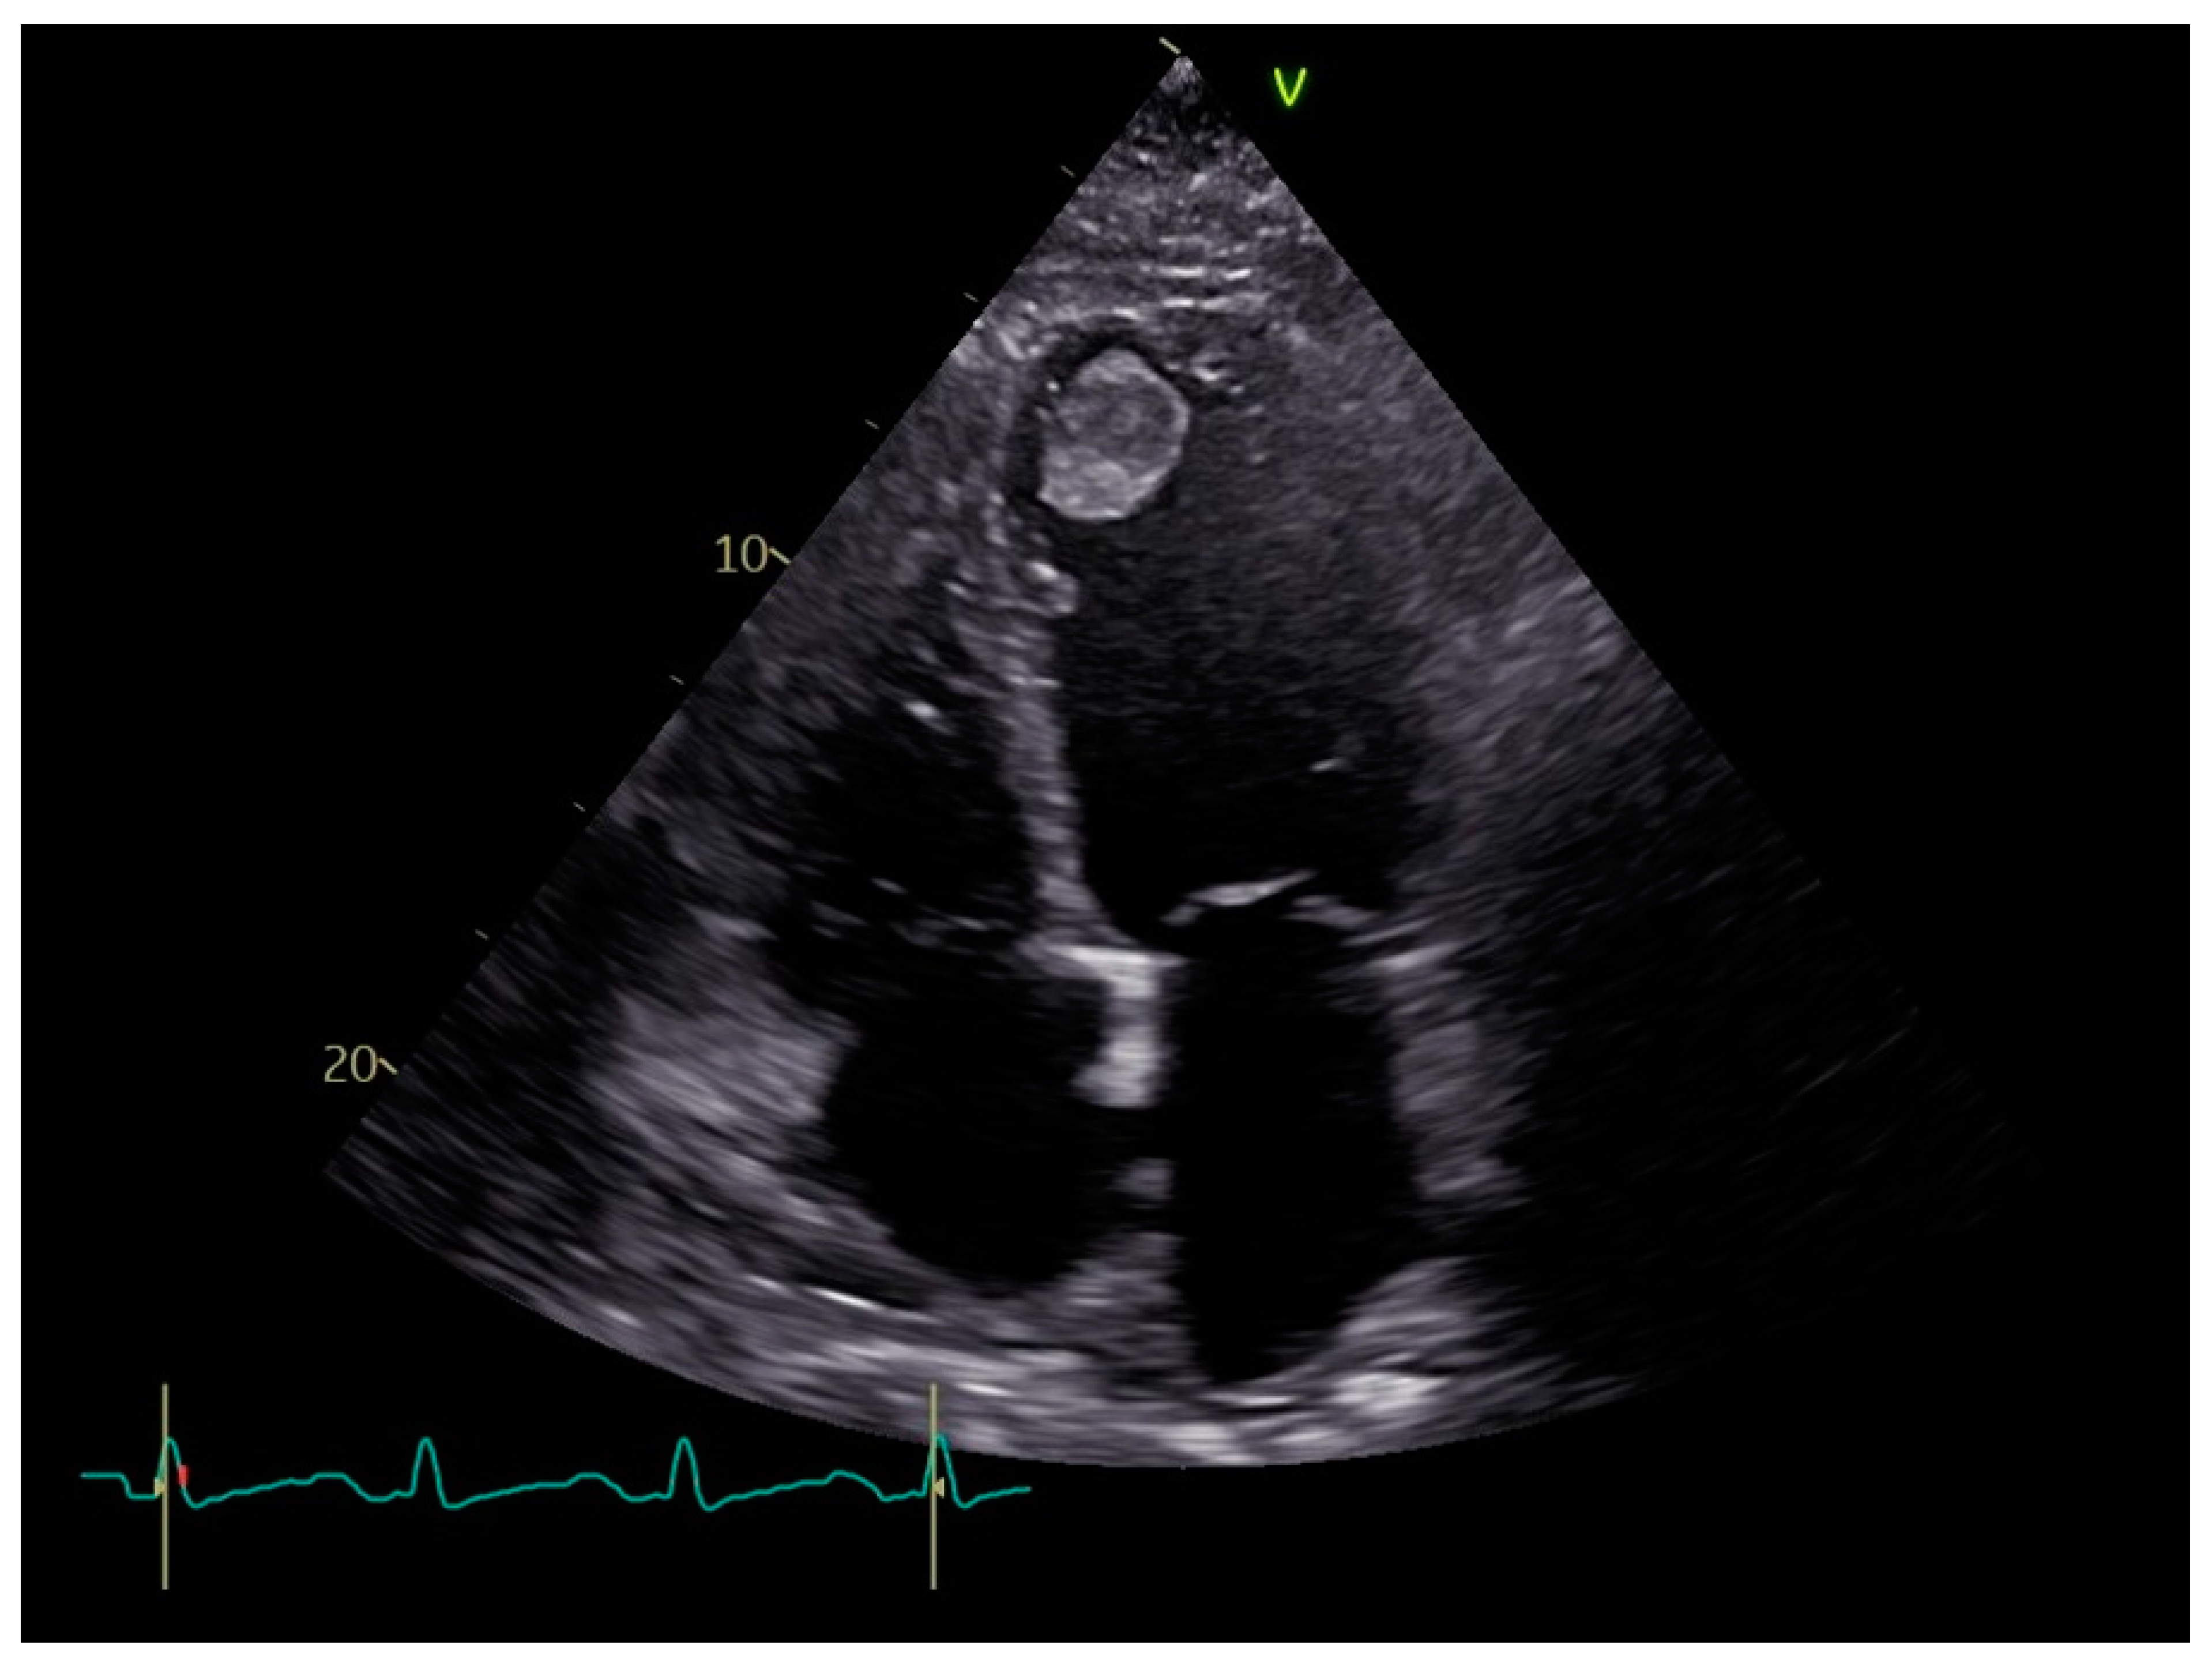

4. Diagnosis